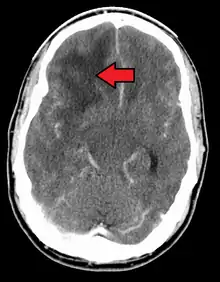

When viewed with MRI, glioblastomas often appear as ring-enhancing lesions. The appearance is not specific, however, as other lesions such as abscess, metastasis, tumefactive multiple sclerosis, and other entities may have a similar appearance.[49] Definitive diagnosis of a suspected GBM on CT or MRI requires a stereotactic biopsy or a craniotomy with tumor resection and pathologic confirmation. Because the tumor grade is based upon the most malignant portion of the tumor, biopsy or subtotal tumor resection can result in undergrading of the lesion. Imaging of tumor blood flow using perfusion MRI and measuring tumor metabolite concentration with MR spectroscopy may add diagnostic value to standard MRI in select cases by showing increased relative cerebral blood volume and increased choline peak, respectively, but pathology remains the gold standard for diagnosis and molecular characterization.